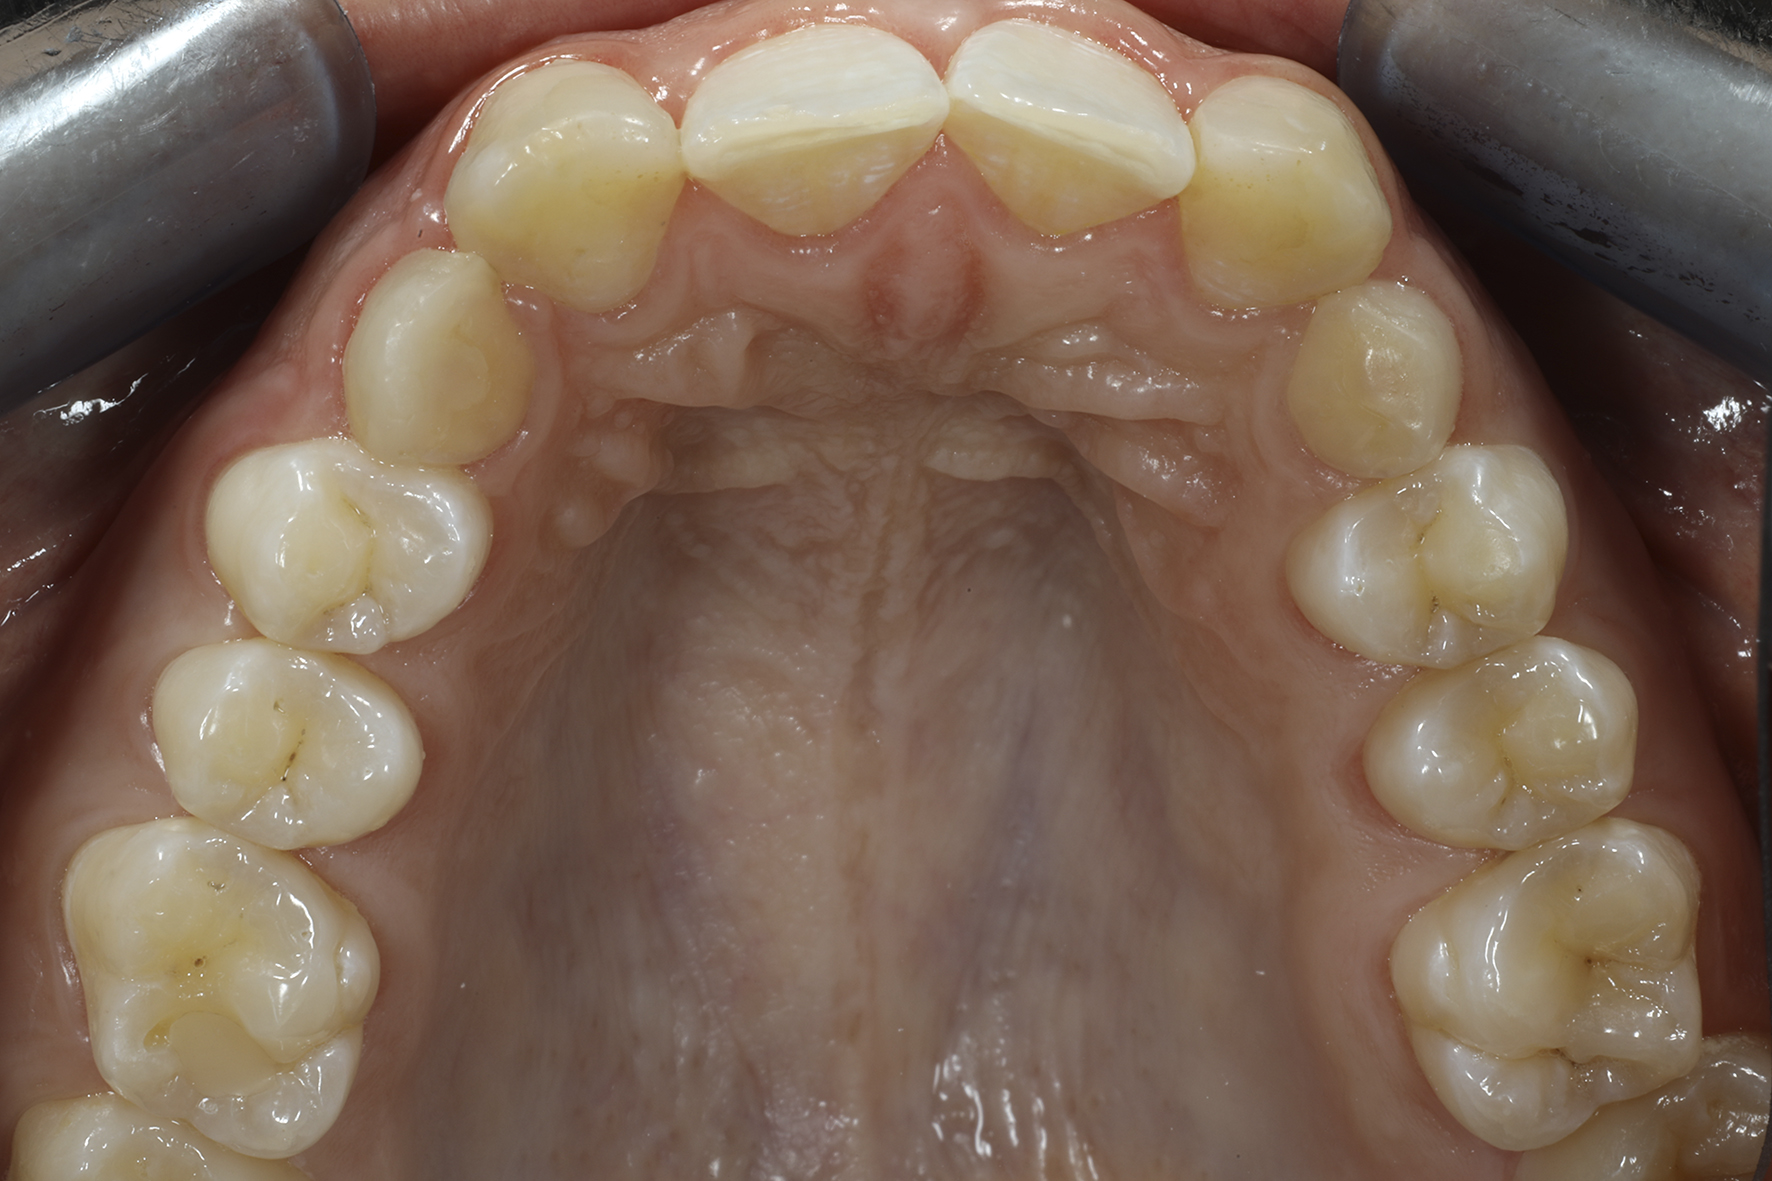

Näkymä okklusaalipeilin kautta nähtynä.